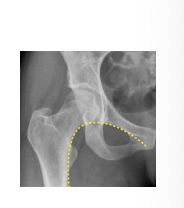

Shenton’s line:

Imaginary curved line along inferior border of superior pubic ramus. Should eb continuous and smooth